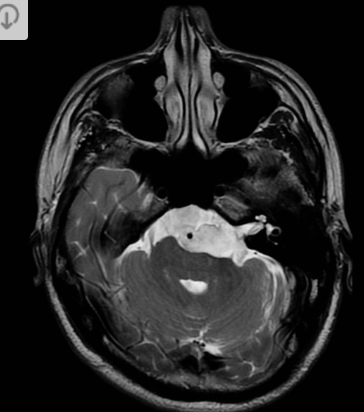

35 anos

Hemangioblastoma